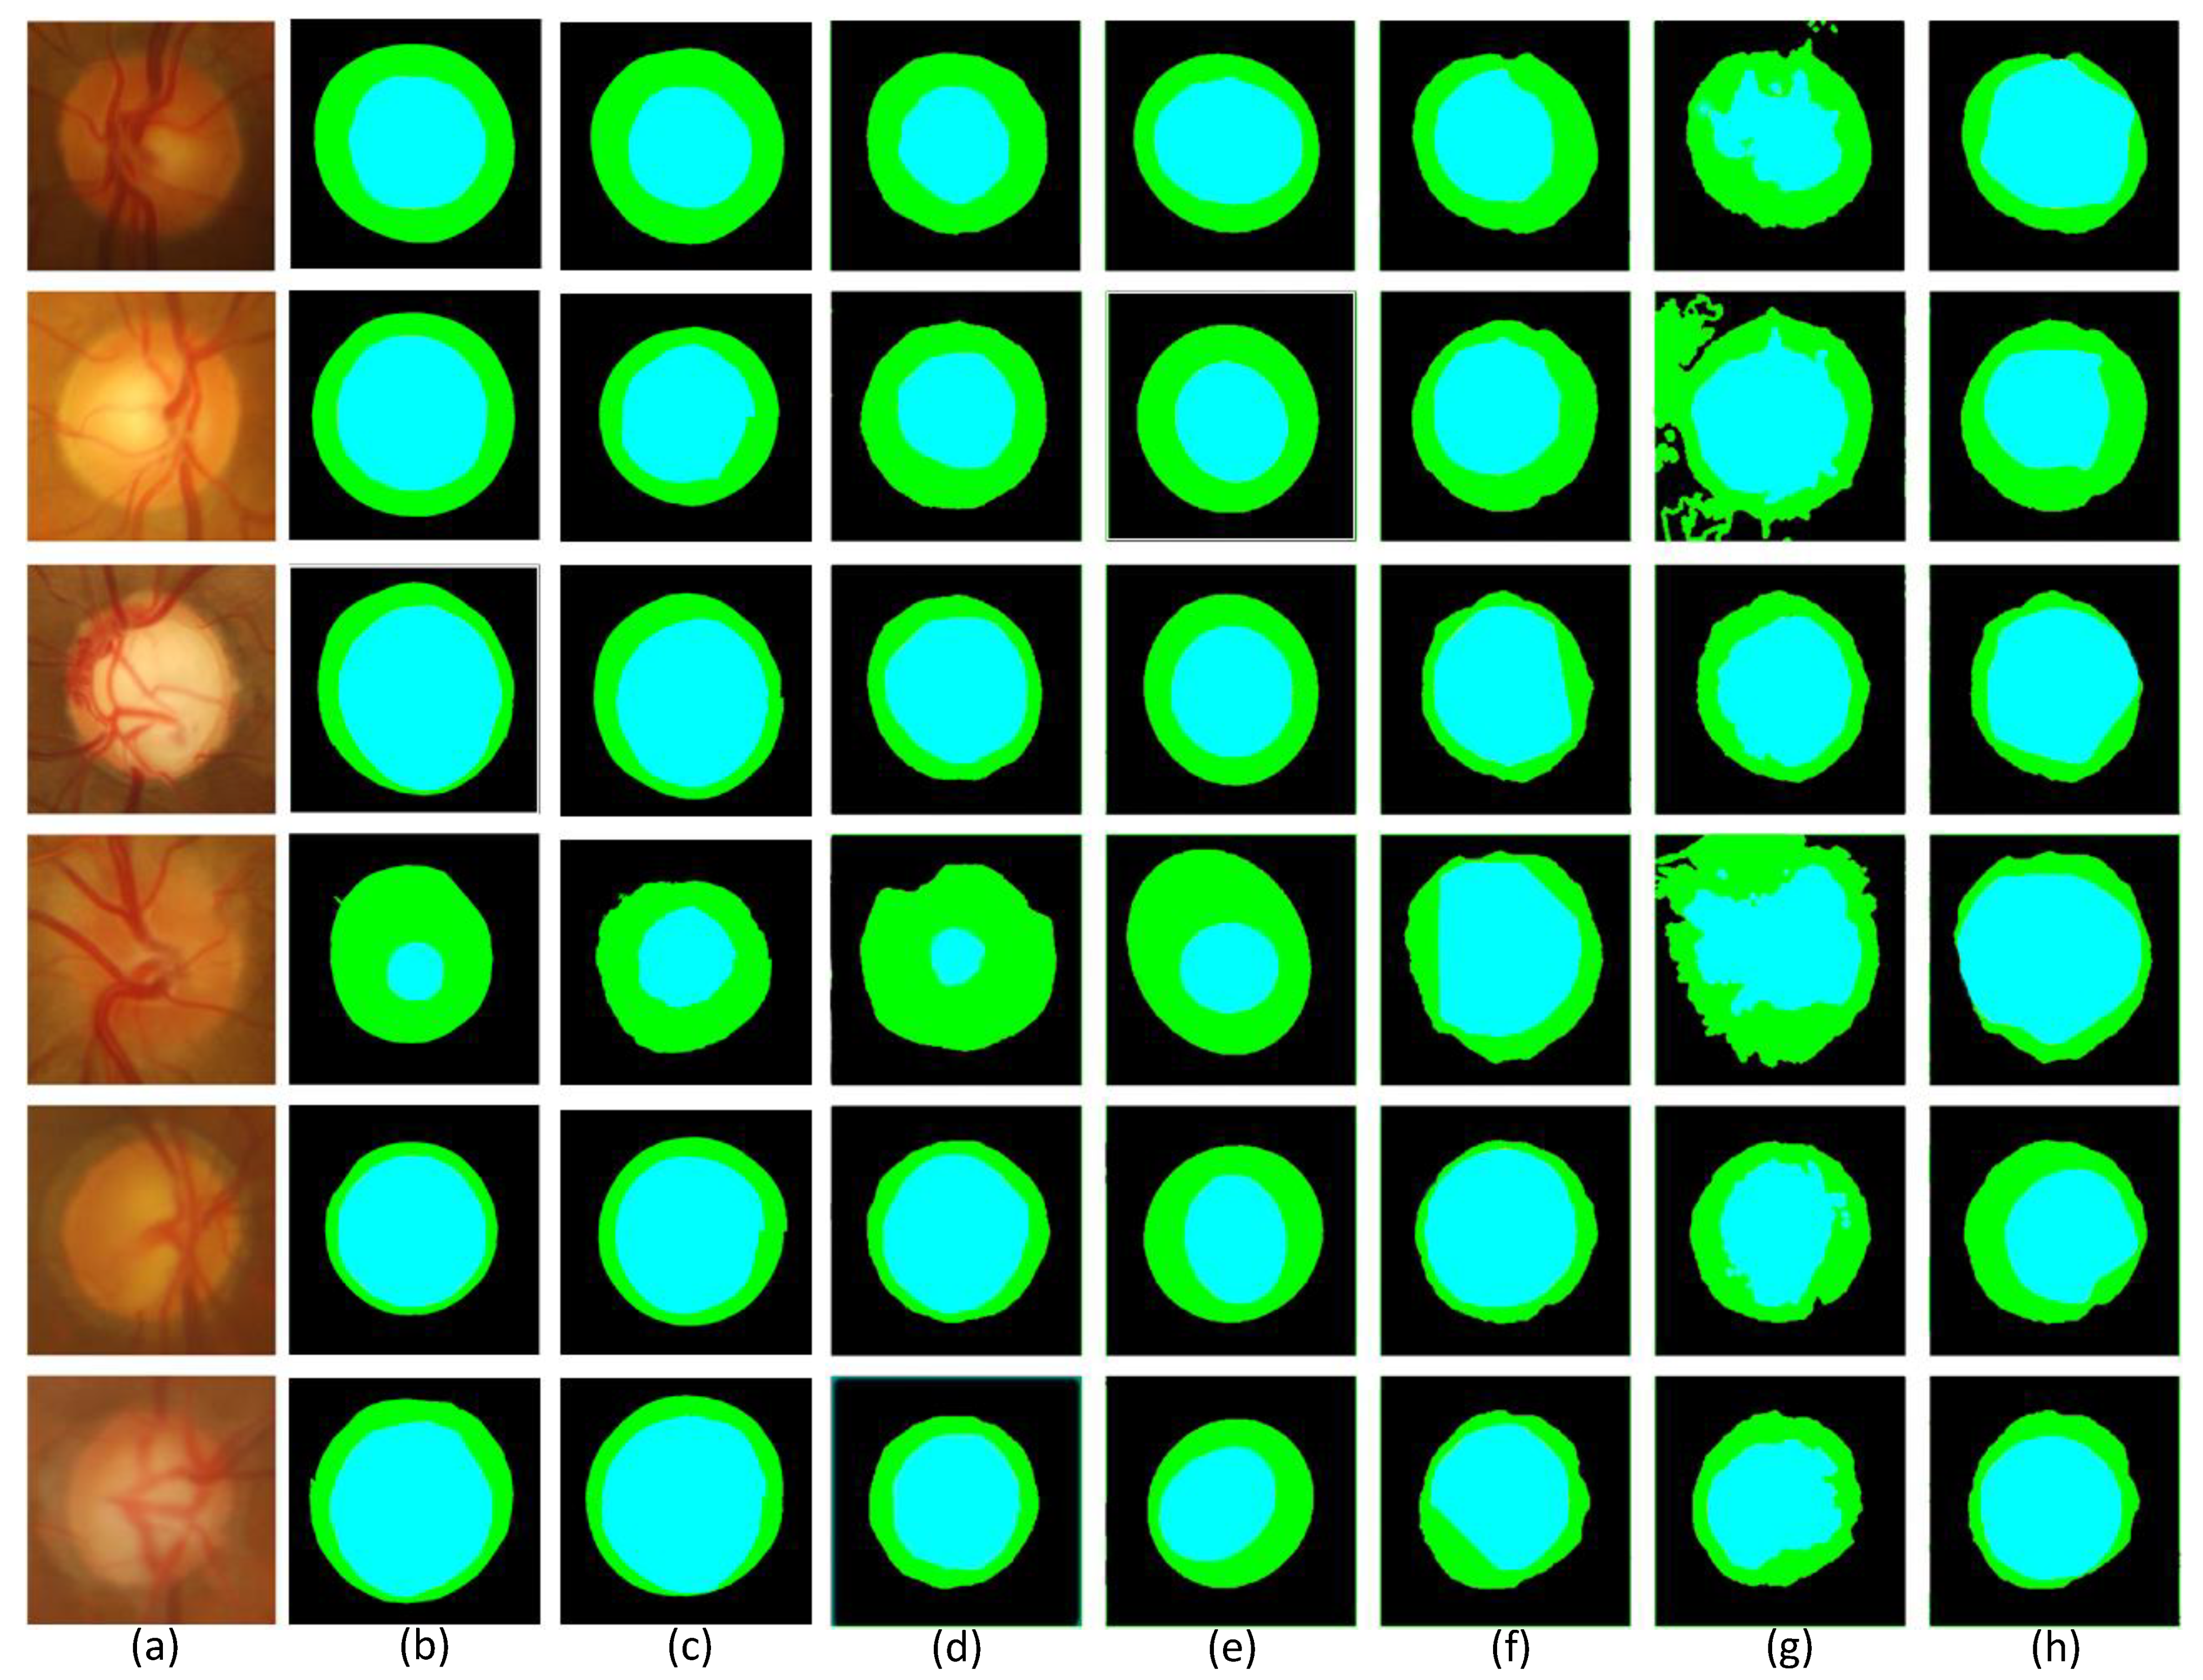

Figure 8.

Comparison of segmentation images of each model in the Drishti-GS1 dataset. (a) Original image (b) Segmentation image of disc (c) Partial segmentation image of disc (d) Segmentation image of cup (e) Partial segmentation image of cup (f) Segmentation image of optic (g) Partial segmentation image of optic.

Each row of Figure 8 shows the visualization segmentation results for the optic disc and optic cup corresponding to each model on the Drishti-GS1 dataset. Since the segmented images were too small to be easily observed, we zoomed in on the visualization results for the optic discs and optic cups.The first row of the figure shows the original image of the optic disc cup along with the corresponding ground truth and the corresponding magnified image. The second row is the segmentation visualization of the baseline network model experiment. The third row is the segmentation visualization of the network model, adding the SMCF module. The fourth row is the segmentation visualization of the network model joining the SRL layer. The fifth row is the segmentation visualization of the network model, adding the MBCM module. The sixth row is the segmentation visualization of MSMB-Net. In addition, we can determine the difference between the different network models by looking at the magnified edges in the optic disc view cup visualization. Comparing the partially enlarged images of different module combinations, we can see the effectiveness of MSMB-Net segmentation. The optic disc cup area is also enlarged and displayed. Through the enlarged image, it can be seen that the contour of the MSMB-Net model is more consistent with the real label during the segmentation of the optic disc. Compared with other combined models, the segmentation contour of the optic cup of the MSMB-Net model is more accurate and perfect than other models.